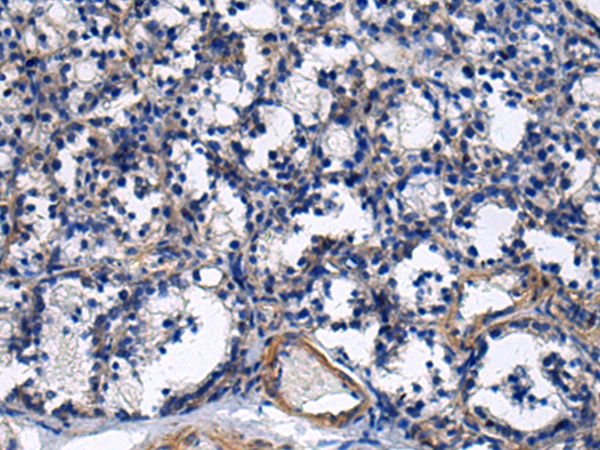

ELISA, IHC |

IHC positive control: |

Human esophagus cancer and Human prostate cancer |

IHC Recommend dilution: |

25-100 |